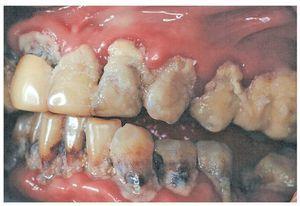

Griffin et al9 concluyeron, tras un metaanálisis de 20 estudios clínicos, que el efecto reductor de la caries (caries coronal) de diferentes medidas de fluorización en adultos se encuentra en aproximadamente el 25%. Leake12 publicó en el año 2001 una serie de recomendaciones basadas en la evidencia para la prevención de la caries radicular y para frenar la progresión de lesiones de caries radicular existentes. Dichas recomendaciones se corresponden con las de los pacientes jóvenes e incluyen el uso de colutorios con fluoruro, la aplicación de un barniz de fluoruro cada tres meses y la aplicación de geles de fluoruro en el hogar, combinada con la aplicación profesional cada tres meses por parte del odontólogo, además de la utilización de pastas dentífricas con fluoruro. Hoy día también sabemos que, con las medidas de fluorización tópicas, se puede detener la progresión de la caries incipiente o evitar la aparición de lesiones de caries. No obstante, también está claro que, en presencia de una alta actividad de caries (falta de higiene oral, consumo muy elevado de azúcar), disminuye la eficacia profiláctica de los fluoruros contra la caries (fig. 5). La caries no es una enfermedad causada por una carencia de fluoruro, sino la consecuencia de un desequilibrio entre los factores preventivos y los factores favorecedores de la caries.

Figura 5. En presencia de unas condiciones altamente cariogénicas en la cavidad oral, ni la aparición ni la progresión de lesiones de caries se pueden evitar solo con medidas de fluorización. La caries no es una enfermedad causada por una carencia de fluoruro.